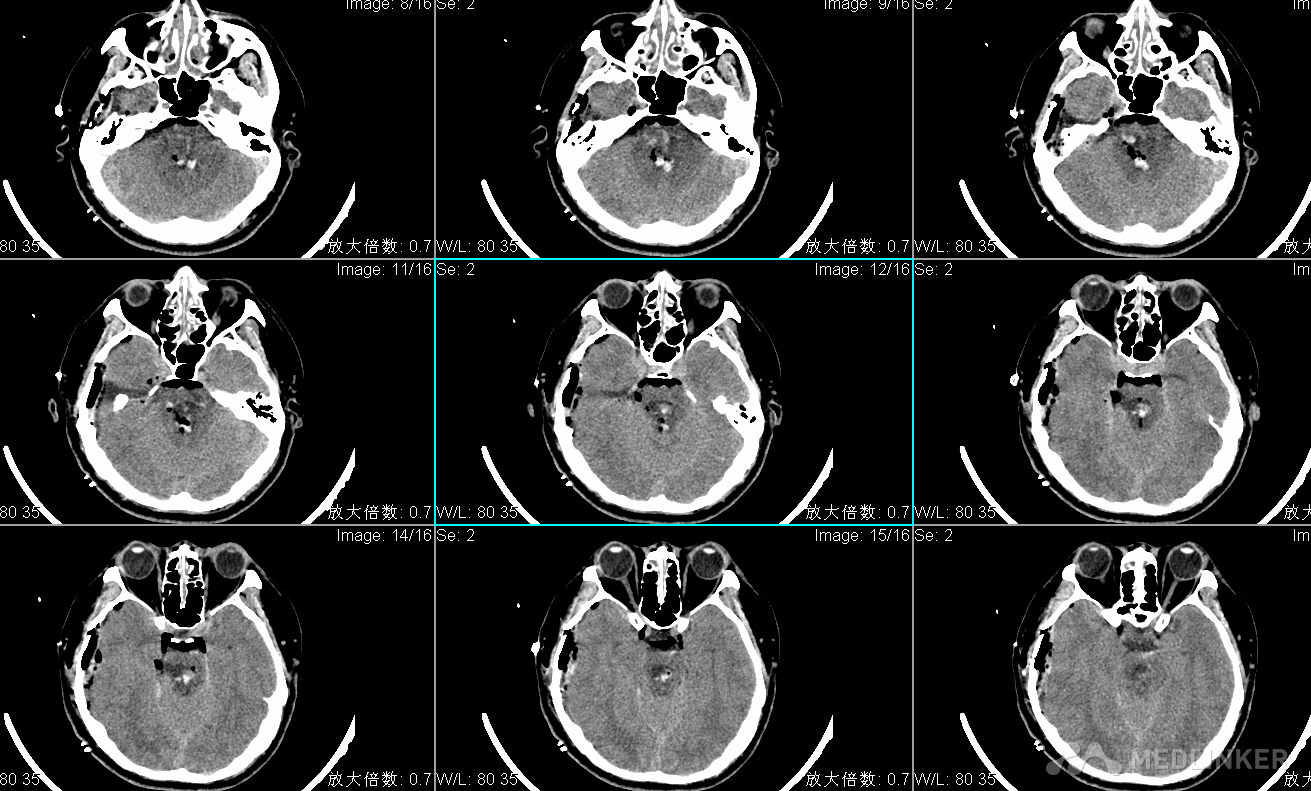

查体:T:36.3℃ P:73次/分R: 20次/分BP:154/107mmHg 嗜睡状态,呼之睁眼,应答切题,四肢可从嘱活动,GCS14分,双侧瞳孔直径左:右=2:2mm,光反射灵敏,可及水平眼震,额纹对称,颈软,左侧肢体4级,右侧肢体肌力5级,肌张力不高,腱反射(++),生理反射存在,双巴氏征(-)。入院头CT显示脑桥出血出血量约2ml。

入院诊断为:1.脑干出血 2.高血压病3级(极高危)3.吸入性肺炎。 入院后给予止血、控制血压及对症支持治疗,患者病情进行性加重,昏迷,四肢刺激强直,自主呼吸消失,复查头CT显示脑干出血多田公式计算约20ml,家属强烈要求手术治疗。